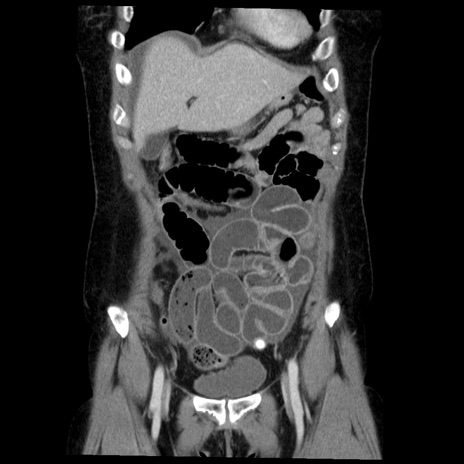

症例6(冠状断像)

【症例】50歳代女性

【主訴】下腹部痛

【現病歴】本日朝より下痢2回あり。 昼食を食べた後、嘔吐3回、下腹部痛認め、症状軽快せず、当院救急搬送。

最終食事:本日昼(生ものなし)。 昨日の夜、刺身を食ぺたとのこと。周囲に同様の症状の者なし。普段、排便は毎日あるとのこと。

【既往歴】卵巣癌術後(8年前に当院で卵巣摘出)

【身体所見】 意識清明、腹部:平坦、腸蠕動音→、やや硬、下腹部自発痛・圧痛あり、反跳痛あり、筋性防御なし。

【データ】WBC 16000、CRP 0.01